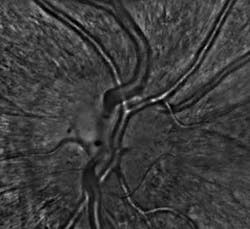

Just recently, the consortium delivered two of three planned prototypes of its Adaptive Optics Flood Illumination Fundus Camera (AO FIFC) for field tests to evaluate their potential for clinical investigations. Initial feedback from the consortium’s medical partners has been positive. “When the first INOVEO prototype reached our hospital, we were immediately startled by its compact size, similar to that of a standard retinal camera,” notes Olivier Roch, MD, at the Hôpital Necker, a children’s hospital in Paris. “While the adaptive-optics systems that we had previously seen in various publications seemed to occupy the surface of a very large desk, the new prototype fit perfectly into our clinical setting. After just a couple of days of training, our medical researchers were able to immediately proceed with the project’s clinical investigation program. The first cellular-resolution images revealed an impressive level of detail that could never have been seen with conventional imaging instruments.”

“The AO FIFC’s high resolution and relatively wide field of view make it an invaluable device for diagnosing macular holes when conventional imaging techniques are unable to confirm the patient’s subjectively reported visual symptoms,” notes Kiyoko Nakashima, MD, from the Hôpital Necker. The macula is responsible for our detailed, sharp vision and, at the early stages of this disorder, changes in visual acuity often occur or straight lines may appear wavy. Because the AO FIFC enables doctors to assess the presence and function of photoreceptors around the macular hole and monitor its two-dimensional progression, this may help them to decide whether a natural regression is likely or if a surgical intervention is required.